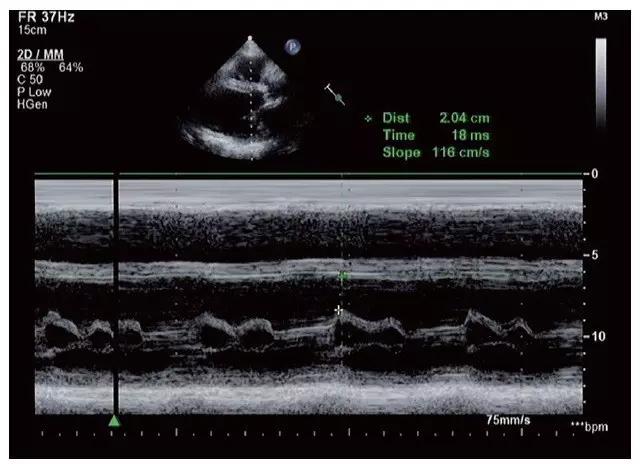

3.瓣膜自身无明显变化,但开放幅度均减低。二尖瓣开放受限,瓣口面积减小,前后叶开放幅度减小,但仍呈镜像运动,EF 斜率减慢,呈“钻石样”改变,E-E 间距< 10mm,与扩大的心腔形成“大心腔,小开口”改变。 二尖瓣前叶与室间隔之间的距离,即E 峰间隔分开距离(E-pointseptal separation,EPSS)明显增大,一般>10mm(图11-1-3)。

图11-1-3 扩张型心肌病EPSS明显增大